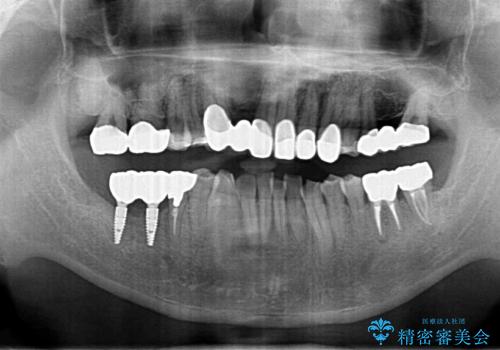

- 短期間で歯並びを治したいとのこと。期間が短ければセラミックでかぶせる治療できれいにするのでも構わない。虫歯の治療もすべてお願いしたいとのことでした。

右下の奥歯は残せない可能性を説明しました。

また、歯並びの矯正をするのではなければ、右上の八重歯は、犬歯を抜くか、奥に入っている歯を抜くかになるとお伝えしました。結果、根の長い犬歯を残して右上の前歯を抜歯しブリッジにしました。また、前歯の神経は極力取らないで治療を行いました。(結果神経を取る治療は前歯には行っておりません)

右下奥歯二本はインプラントにしました。(横浜桜木町歯科院長 大元先生による)

また、銀歯はすべてやり直しを行い、セラミックでやり替えを行いました。

前歯の治療を先に行い、見た目を改善した後、奥歯の治療を行いました。